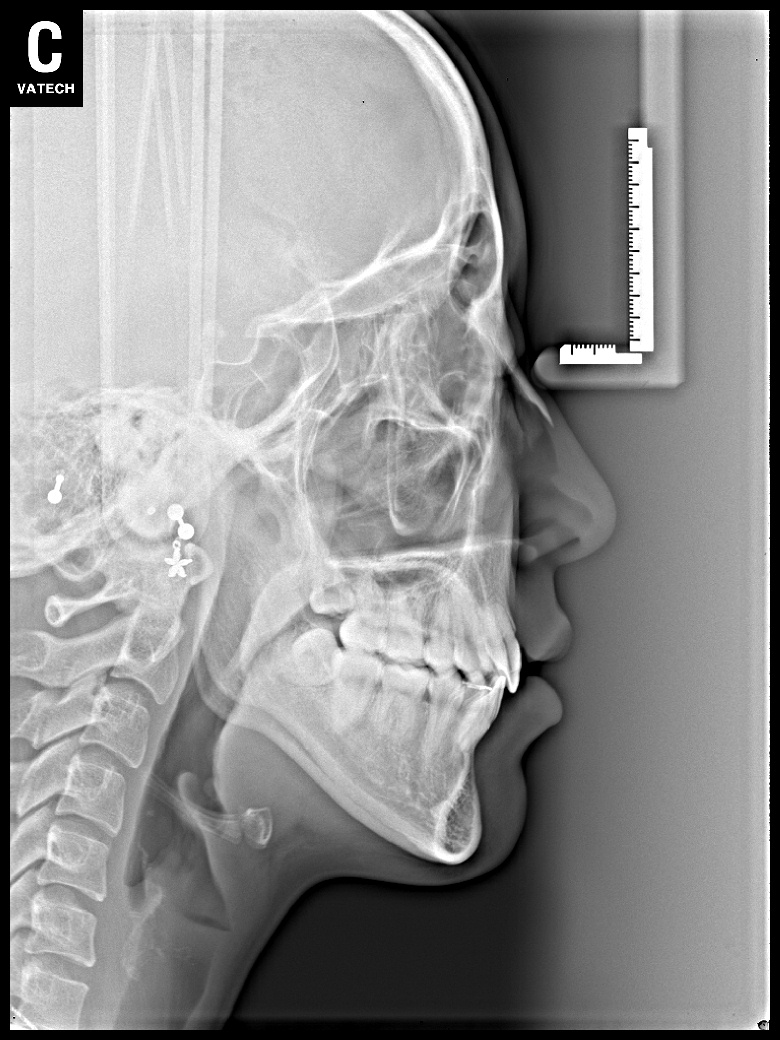

치료 후 사진입니다.